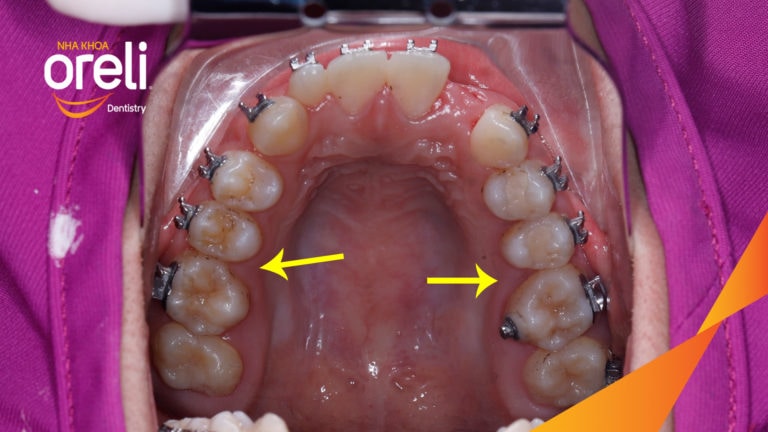

Ca niềng răng sai khớp cắn hạng 3 móm chen chúc kèm di gần răng số 7 8 thay thế răng 6 ở Oreli Niềng răngChen chúcDi gần răng 7 8Móm Xem thêm